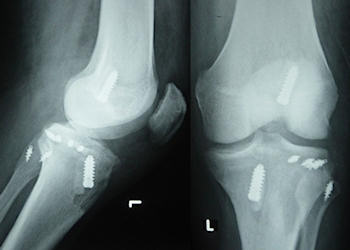

Bütün olgularda direkt grafiler elde olunmalıdır. Direkt grafilerde diz çıkığı (spontan redükte olmamışsa), Fibula başından avülziyon kırığı, Segond kırığı (Antero-lateral kapsüler avülziyon) ve tibial rim kırıkları saptanabilir.

Günümüzde geçerli olan teknik, LaPrade tarafından tarif edilen, bütün hasarlı yapıların ayrı ayrı anatomik rekonstrüksiyonudur (LaPrade RF. Am J Sports Med 2004). Bu teknikte iki ayrı allogreft ile, dış yan bağ, Popliteus ve Popliteo-fibuler ligament anatomik olarak rekonstrükte edilir. Tespit biyobozunur vidalar ve staple ile yapılır.